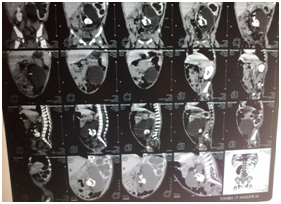

Clinical examination of the patient revealed soft abdominal mass occupying the left hemi-abdomen. Ultrasonography exam had shown a left hydronephrosis associated with polycystic mass measuring 10x15cm containing multiple calcifications. CT scan exam revealed a left hydronephrosis with a thin renal cortex associated with a well-capsulated and heterogeneous mass containing multiple calcifications, measuring 82x66x59mm, localized in the retro-peritoneum space and adherent to the lumbar vertebral column and the left iliac crest, pushing away the aorta and the inferior vena cava to the right side of the abdomen and compressing the left ureter (Figure 1). We suspected with teratoma. Contrast multislice computed tomography of the abdomen was done and it shew a bony mass lying on the left iliac crest and is adherent to the fifth lumbar vertebra and it receives blood perfusion through small vessel arising from the aorta (Figure 2). On surgical laparotomy and exploration using transverse left infra-umbilical incision, we found a large retro-peritoneal cystic mass adherent to the 5th lumbar vertebra and the left iliac crest, pushing the aorta and the inferior vena cava to the right side. There was no adherence with the left kidney but the ureter was compressed causing hydronephrosis.

Figure 1 CT scan shows well-limited cystic mass located in the left lower retroperitoneum containing multiple calcifications provoking a left major hydronephrosis.